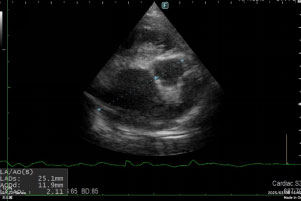

以上より、僧帽弁閉鎖不全症と心原性肺水腫と診断しました。

呼吸状態が悪く、自宅での管理が難しいため、酸素室で入院しながら治療を行いました。

治療は、利尿剤や強心剤を投与しました。

幸い治療が奏功し、呼吸状態が良くなり、レントゲン検査でも肺の透過性が改善しました。(図4参照)

図4